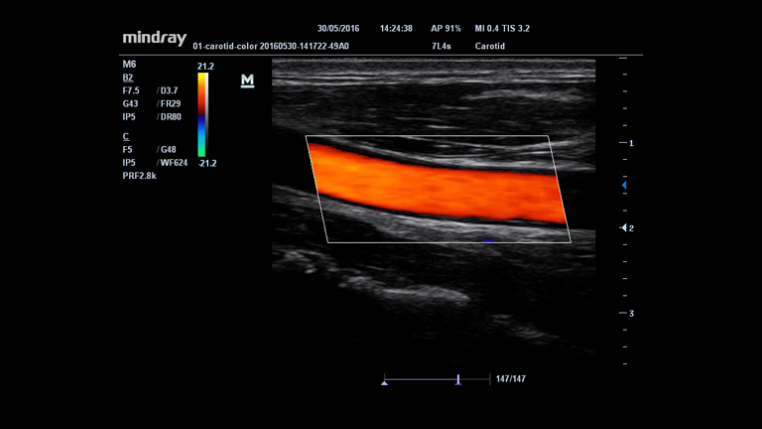

Funci√≥n √Їnica de Mindray: Una funci√≥n √Їnica de Mindray: realice un seguimiento continuo del flujo de color y optimice la mejor posici√≥n del cuadro de color y el mejor √°ngulo en la adquisici√≥n de im√°genes en tiempo real.